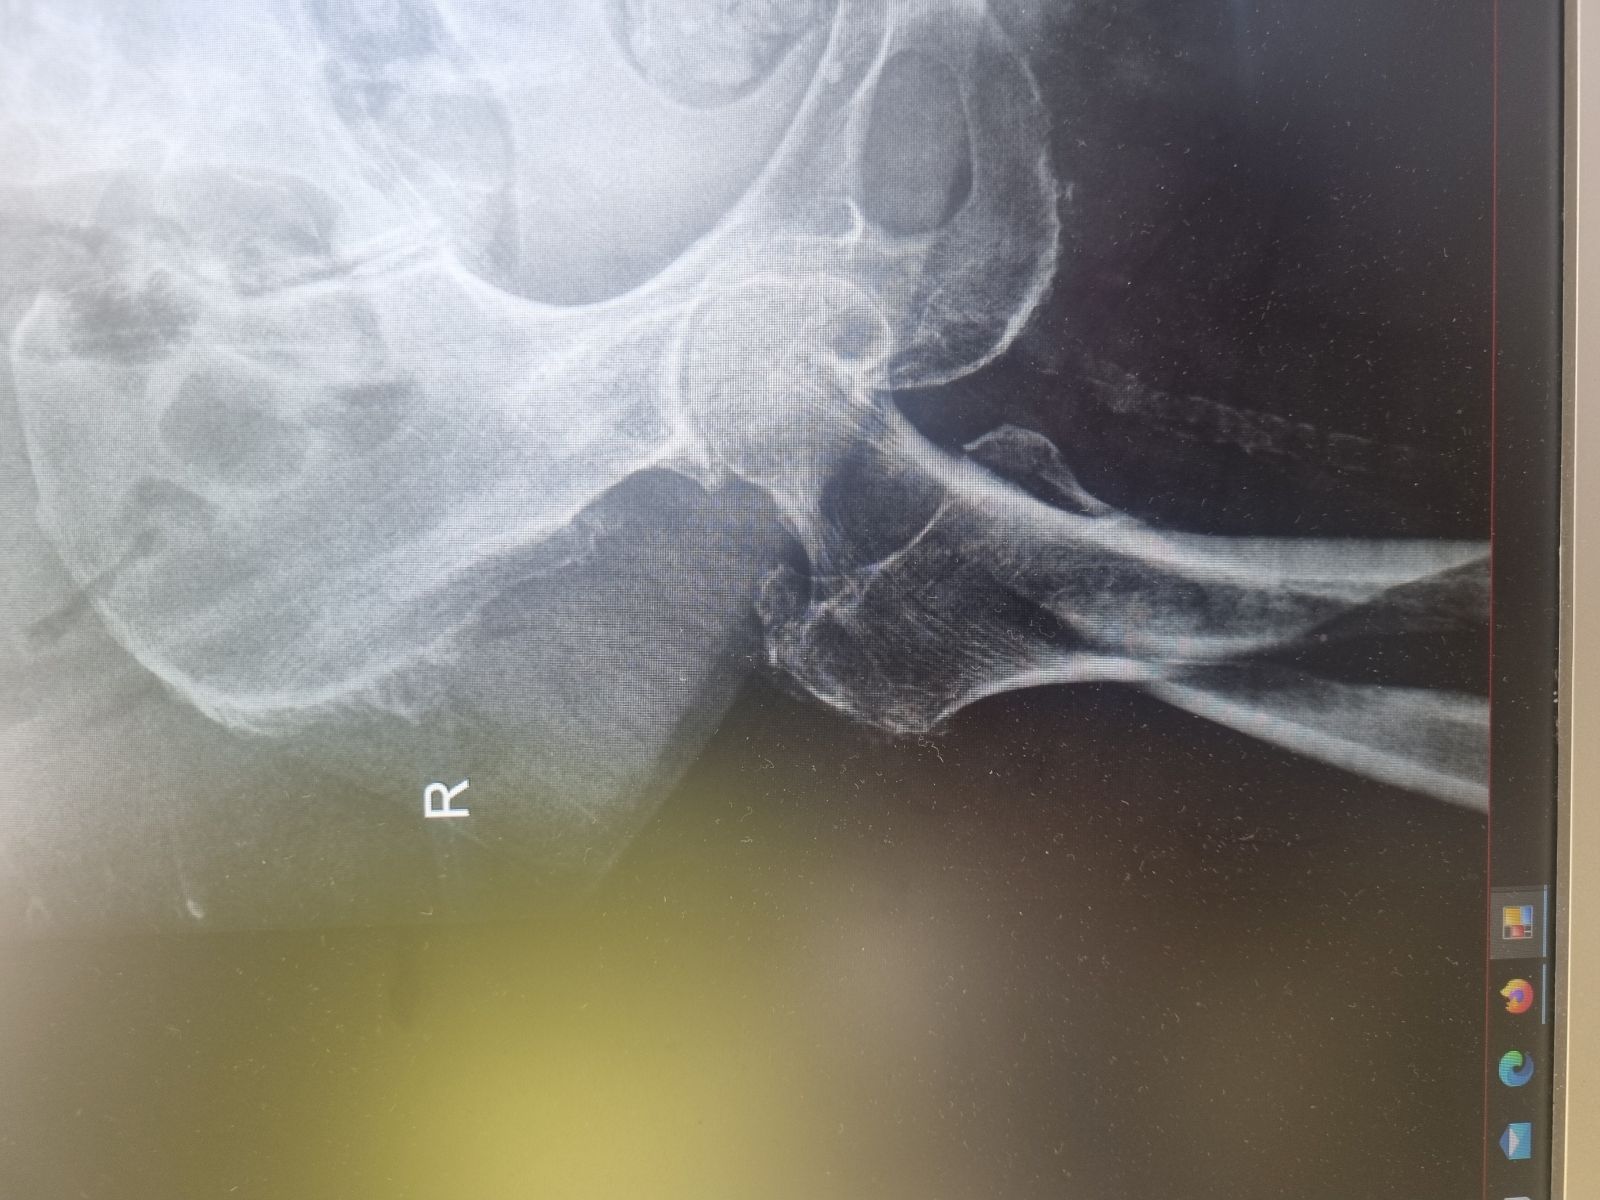

Miednica i kończyna dolna